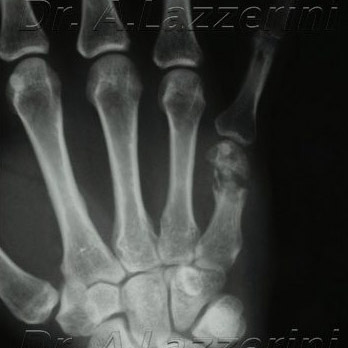

Pseudoartrosi del 5° metacarpale